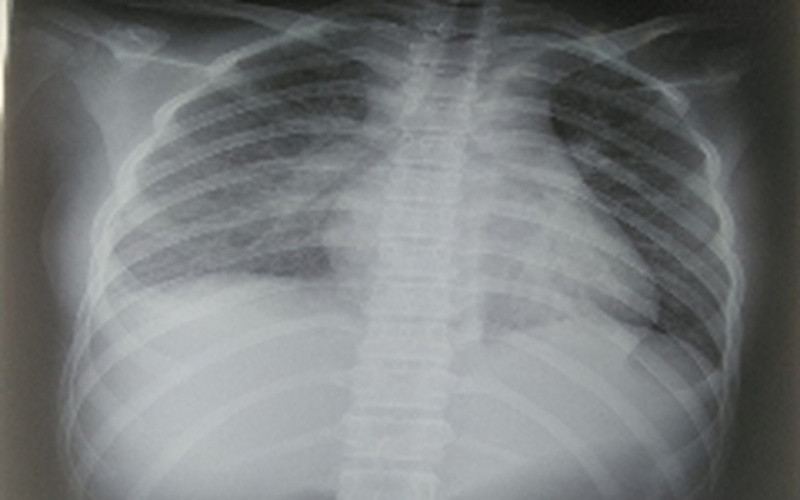

Các xét nghiệm cho thấy bệnh nhi bị tổn thương nhiều cơ quan, trong đó, phổi có tổn thương mờ dạng kẽ vùng rốn phổi 2 bên; tim có tràn dịch màng ngoài tim; các chỉ số men gan cũng tăng gấp 2 lần. Đặc biệt là các chỉ số viêm tăng rất cao.